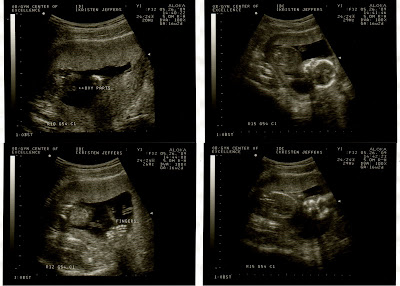

WE'RE HAVING A BOY!!!!!!!!!!!!!!!! Hip Hip Hooray!!!!! Dave and I are both beyond excited, and can't wait to meet Mr. Bean Sprout.

My appointment was at 2:30 and if I wouldn't have had to work today, I may have just showed up at the doctor's office as soon as they opened. As soon as Dr. Brody put the wand to my belly, Bean Sprout was in position to tell us that he is all boy. Today he wasn't nearly as squirmy as usual and (obviously) we saw more than we had seen in the other ultrasounds. We saw the chambers of the heart beating, individual fingers, the skull, and the boy parts. Dr. Brody said that he is 99% sure that he's a he, so I take that as enough to get super duper excited. I had a blood work taken to test for the risk of spina bifida and Downs Syndrome and we'll know if there is an increase risk of either in a week. More than I wanted a little boy, I want a healthy little baby. Hopefully he will be really healthy and really happy.